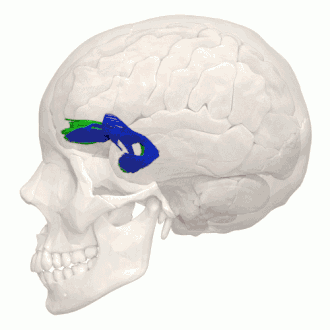

Tractography showing uncinate fasciculus. -

Animation of tractography data. Blue is the left, green is the right.